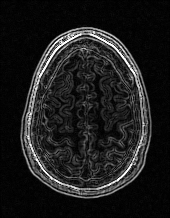

EPN is utilized to provide edge priors for later reconstruction, so the quality of the predicted edges is very important. In Fig. 10, we provide some qualitative results of the predicted edges of EPN on three multi-coil datasets. Among them, the GT edges are extracted using the Sobel operator. As can be seen from the images, our proposed EPN can predict an approximate contour for the overall subject and can reconstruct accurate edges close to the GT edges under two acceleration factors. This fully verifies the effectiveness and excellence of the proposed EPN.

(a)

(b)

(c)

(d)